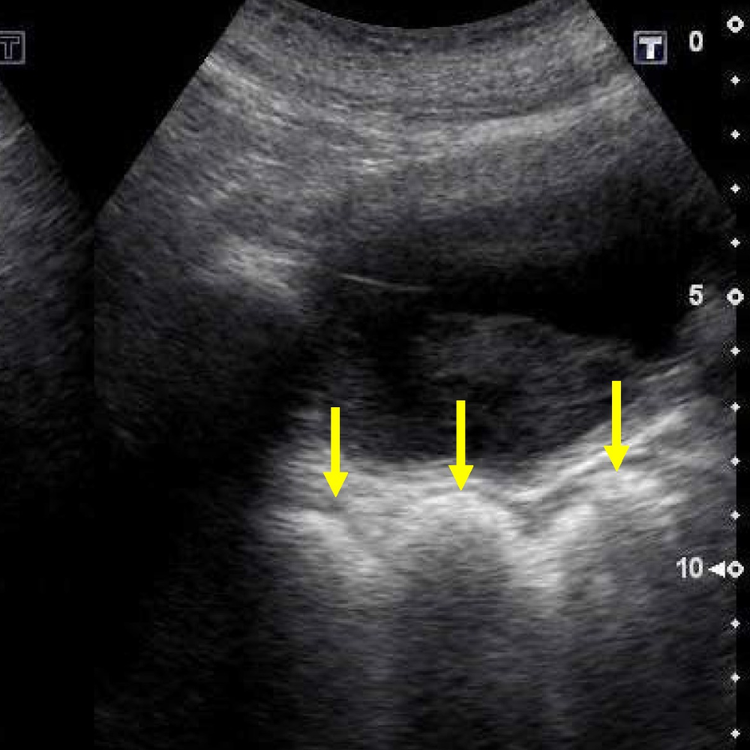

Confirmer la rétention en quelques secondes.